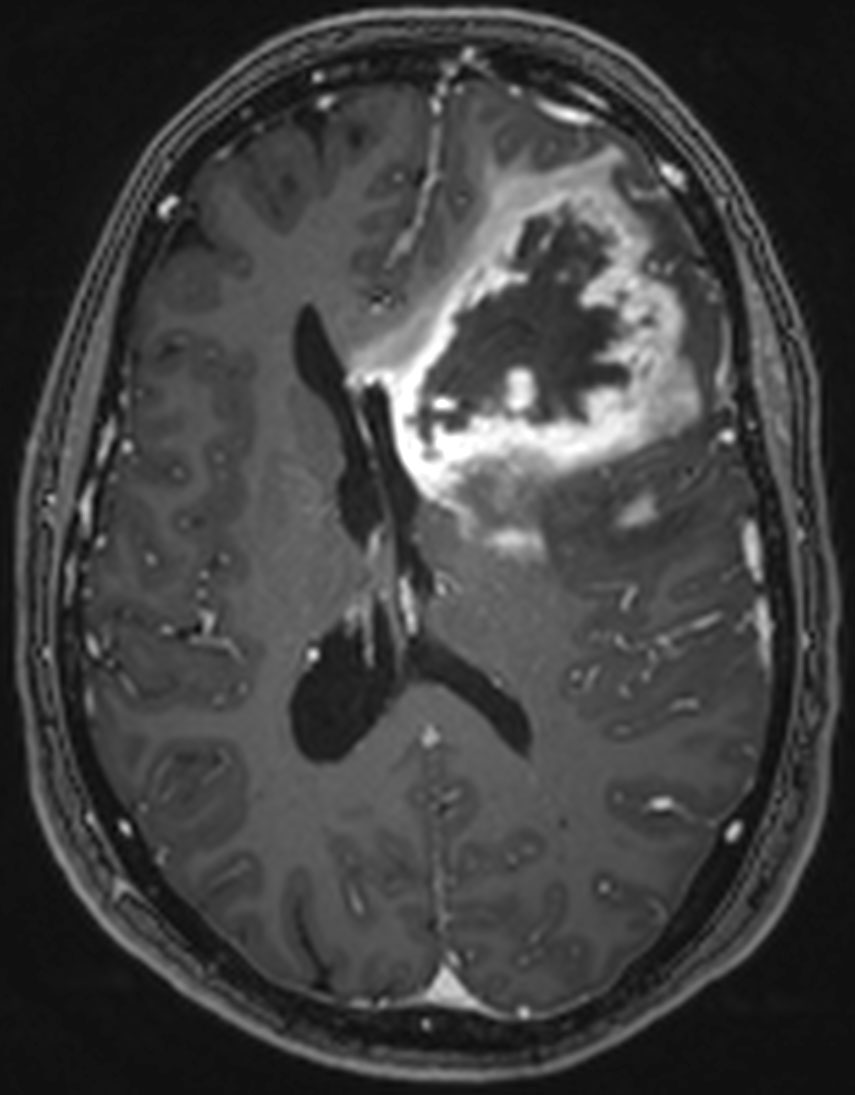

Billedet er stillet til rådighed af afdelingslæge Anna Tietze, Aarhus Universitetshospital.

“We have developed an MRI technique which reveals how a patient will respond to the treatment that inhibits the growth of new blood vessels to the tumour. The technique allows us to only select the patients who will actually benefit from the treatment and to quickly initiate or intensify other treatments for non-responding patients,” says Kim Mouridsen, Associate Professor at Aarhus University and head of the research group Neuroimaging Methods at MINDLab, Aarhus University.

According to Kim Mouridsen, the new technique – Vessel Architectural Imaging – is an important step towards better treatment:

“Getting more knowledge about what the blood vessels in the tumour look like will also give us a better understanding of the mechanisms which are decisive for the efficacy of the treatment. And understanding these mechanisms is precisely what we need to be able to develop and improve the treatment of brain tumours in general.”